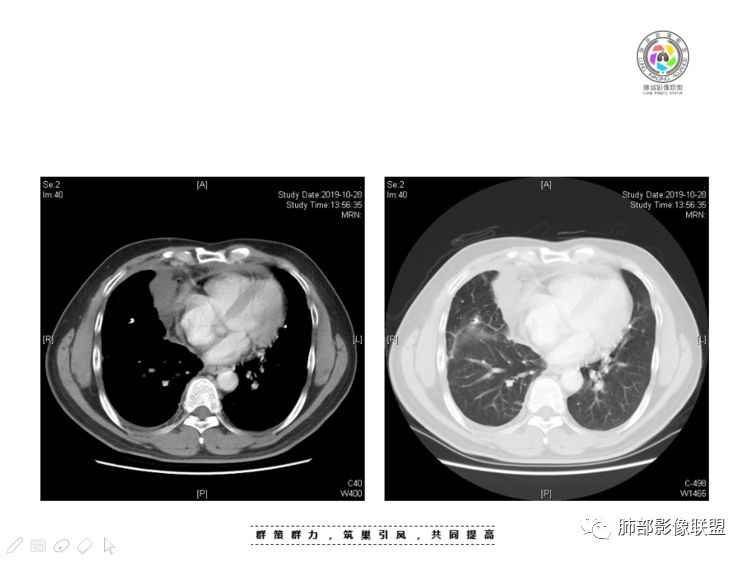

穿越七海的风:右前纵隔占位,恶性肿瘤,生殖来源?右肺实变是占位or肺不张?考虑为部分肺不张FeNo:右前纵隔占位,右肺结节,胸膜凹陷,小尾巴,右肺不张,考虑恶性杨旭华:恶性,前纵隔肿物,与血管关系密切,上腔静脉变窄,右肺野一元论考虑叶间裂增厚,恶性胸膜间皮瘤可能大小丽:到底是纵隔来源还是胸膜来源?我怎么倾向于胸膜来源,和叶间胸膜关系密切,而且纵隔内上腔静脉是向内侧推移。胸膜肿瘤(间皮瘤?SFT?)包裹性胸腔积液?马春平(张家港市一院胸外科):前纵隔占位,左无名受压,右大量胸腔积液可能是胸导管汇入处侵犯受压,考虑纵隔鳞癌孙冰伟:右上纵隔占位,也感觉和叶间胸膜关系密切,右侧胸膜局限性增厚,考虑恶性可能性大灵:前纵隔占位,血性胸水,胸膜凹凸不平,查见肿瘤细胞,结合免疫组化考虑胸腺癌。鉴别胸膜间皮瘤。采莲:右前上纵膈旁可见类圆形肿块,纵隔血管内移,感觉来源于胸膜,肿块内密度低,似水样密度,右侧胸膜广泛增厚,少量胸腔积液。心包少量积液。考虑胸膜间皮瘤,鉴别肺癌并胸膜转移?水晶石头:患者中年男性,胸闷15天。有“高血压、慢性肾小球肾炎”病史。查肿瘤标志物正常,胸水提示渗出液,胸水病理查见瘤细胞。胸部CT:右肺上叶后段结节、斑片影,见胸膜牵拉、包裹积液及部分纤维条索灶,似见卫星灶,右侧胸膜增厚。前纵隔脂肪密度增厚,右侧可见类圆形低密度(液体)肿块,边缘光滑。综合考虑右肺腺癌并胸膜转移,结核可能。周太狼:考虑纵隔胸膜来源肿瘤,恶性,胸膜间皮瘤伴转移?徐飞:中年男性,影像为右侧胸腔及叶间积液,叶间胸膜增厚轻度强化。前纵隔右侧心缘旁团块,可见坏死。胸水见癌细胞,综合考虑恶性,胸腺癌伴转移。小赵:中年男性,血性胸水,常规查见癌细胞,李凡他实验阳性。胸部CT示前纵隔见不均匀密度影,与邻近大血管分界不清,囊变坏死明显,增强扫描呈不均匀强化,心包及右侧胸膜增厚,并心包及右侧胸腔少量积液。综合考虑胸腺癌。右肺中叶病变周围见多发纤维条索,支气管部分进入病灶,考虑炎性病变。流心明智:患者,男性,50岁。胸闷15天。高血压20年,慢性肾小球肾炎15年。肿标正常,胸水提示渗出液,胸水查见癌细胞。胸部CT:右肺肿块影,斑片影,索条影,可见胸膜牵拉、多发包裹积液,纵隔上腔静脉受累,心包受累。综合考虑:ROSE似腺?考虑右肺腺癌并胸膜转移,心包受累。鉴别胸腺Ca、淋巴瘤,纵隔病变不懂,等老师们精彩分析。王秀仙:前纵膈囊实性肿块,与纵膈分界不清,心脏大血管及上腔静脉受压向内后移,右侧后胸膜、侧胸膜增厚,右侧叶间裂不规则增厚,心包积液,根据腔静脉移位情况,考虑纵膈胸膜来源恶性肿瘤,胸膜间皮瘤?鉴别胸腺癌并胸膜转移。高广飞:上纵隔占位,右侧叶间胸腔积液,需考虑恶性自信人生:多发囊实性病灶,包裹性积液,考虑胸膜来源 只是没有看到壁结节,恶性胸膜间皮瘤巴伟:前上纵隔占位,胸膜及心包结节,考虑胸腺瘤或癌,右肺病灶,先考虑陈旧炎性病变。Lenle董:前纵隔占位,部分边缘模糊,病灶内囊变?坏死?上腔静脉受侵,考虑胸腺癌;叶间片状影,强化明显,炎性考虑。常志强:前纵隔囊实混杂密度肿块,边界不清,实性部分强化明显,结合胸水内见癌细胞,考虑恶性肿瘤伴转移。飞鹰行动:前纵隔占位,软组织密度及囊性密度,实性部分密度均匀,致密,病灶与周围血管分界不清,增强后病灶强化有类似不温不火强化,部分血管受侵犯,右肺见肿块样病变及条索状病变,一元论,考虑淋巴瘤,二元论,考虑胸腺瘤B2—B3伴右肺病变。尽量一元论考虑,淋巴瘤可能。看图说话:右肺索条病灶,边缘膨隆,胸膜牵拉,考虑右肺癌伴胸膜转移。晨:前纵隔囊实性肿块,与纵隔分界不清,右侧后胸膜、侧胸膜增厚,右侧叶间裂不规则增厚,考虑纵隔胸膜来源恶性肿瘤,考虑胸腺癌并胸膜转移。丽:中年男性,前纵隔囊实性肿块,呈偏心性生长,临近大血管受压推移,增强后实性部分不均匀强化,心包可见条形积液,考虑胸膜来源恶性肿瘤,胸腺癌可能大。另右肺多发斑片状高密度影及实变密度影,实变影呈均匀强化,右侧胸膜局限性增厚,考虑炎性病变。小飞:右前纵隔囊实性占位,实性部分明显强化,右侧叶间胸膜增厚,右侧胸腔积液,心包积液,考虑恶性胸腺瘤!尘缘:支持恶性胸腺瘤(囊实性肿块,实性强化,且侵犯纵隔,脂肪间隙模糊)伴肺内及胸膜转移。浪迹天涯:考虑侵袭性胸腺瘤——胸腺前纵隔占位,周围脂肪间隙模糊不清。尘缘:不除外另一种可能:二元,肺内腺癌合并胸膜转移,纵隔的畸胎瘤可能。一米阳光:晨读中年男性,右肺结节影,叶间裂及胸膜增厚牵拉,右侧胸水。心包多发结节改变。胸水查见癌细胞。考虑,腺癌并转移。鉴别,胸膜间皮瘤并转移前纵隔囊实性占位,二元考虑。心灵鸡汤:老年男性,右肺中叶外段长条状软组织密度影,边缘膨隆,邻近胸膜牵拉,部分胸膜有栽脏,右中叶外侧段支气管堵塞,常规考虑恶性肿瘤,腺癌可能,结核、鳞癌不除外,另右肺上叶斑片影,小叶性肺不张?右前纵隔囊实性不规则形密度影,其内见部分脂肪样极低密度影,与邻近血管边界不清,心包外膜有侵犯,增强未见纵隔窗平扫,实性及分隔见增化,其内低密度影未强化,考虑低度恶性纵隔肿瘤,间皮瘤可能,畸胎瘤、淋巴瘤待排,建议支气管镜及穿刺活检。曹志勇:右前纵隔考虑来源于胸膜的恶性肿瘤,右肺内病灶考虑鳞癌,二元德芙~云味:中年男性,右肺见结节、斑片影,右侧包裹积液、胸膜牵拉,纤维条索,前纵隔囊性占位,考虑腺癌、并转移。欧阳英:右前中纵隔囊实性肿块及右肺内结节灶,支持恶性肿瘤,胸腺癌并肺内转移可能张延军:前纵隔见不规则软组织影,密度不均,右侧缘见囊变区,纵膈及侧胸壁胸膜增厚,增强呈不均匀强化,右肺中叶见结节灶,近段支气管阻塞,叶间胸膜不规则增厚,考虑1:右肺中叶腺癌伴纵膈及胸膜转移;2:前纵膈侵袭性胸腺瘤并胸膜侵犯,中叶炎性改变?彭君:老年,前纵隔占位 ,坏死边缘清, 侵犯心包 右侧胸膜及叶间胸膜结节 ,少量胸水, cea不高 ,考虑恶性, 间皮瘤可能 ,转移待除外。毛勤香:恶性没问题,胸水查见癌细胞,一元还是2元,右肺中叶肿块,边缘毛糙,局部似有毛刺,周围有粘连,右侧胸膜腔少量积液,胸膜增厚多发结节,含叶间裂结节,纵膈脂肪间隙模糊,纵膈胸膜增厚,心包增厚积液,右前那个类圆形低密度肿块,纵膈血管内移,我考虑胸膜来源可能性大,综合考虑,一元肺腺癌并多发转移,二元考虑胸膜间皮瘤并多发转移,肺内炎症不张。

我认为囊张力高,积液中的气体均在周围,外侧、下方,囊内有间隔:各腔密度不一致;提示:囊腔属于前纵隔,不是包裹性积液;现在的问题:囊腔与内侧的病灶是否是一体的

南边:我总觉得这个纵隔内不像是一个肿块的改变,扁平,周围蔓延:有符合炎性的的特点,或者肿瘤的侵犯;但是肿瘤的侵犯,不大符合,实性部位的边缘过于柔和,没有毛糙的侵犯边缘。

肺内结节,近端支气管堵塞狭窄

整体边缘收缩,部分膨隆

炎性要考虑,但恶性不能排除

1、右肺内病灶,病灶呈结节样,边缘欠规则,局部膨隆,叶间裂胸膜牵拉凹陷,再看相应支气管腔堵塞截断,临床资料胸水中查到癌细胞,均提示病灶倾向恶性,腺癌的病理意见与之相吻合。

2、前纵隔内病灶囊实性混杂密度病灶,囊性病灶主要位于右侧,张力较高,有分隔影,囊壁右侧缘光整,病灶左侧实性部分边界不清明显强化,病灶肺瘤交界面大部分边界清楚,部分模糊。

胸腺瘤/胸腺癌:病灶内那么大的囊,常规考虑B型以上胸腺瘤,囊内有分隔影,病灶周围脂肪间隙模糊,常规考虑侵袭性胸腺瘤或胸腺癌,若侵袭性胸腺瘤,常侵犯胸膜、心包,很少累及肺。胸腺癌易侵犯胸膜、肺并纵隔淋巴结及远处转移。但肺内腺癌形态更符合原发灶。胸膜及叶间裂转移则即可来自肺,也可来自胸腺癌。